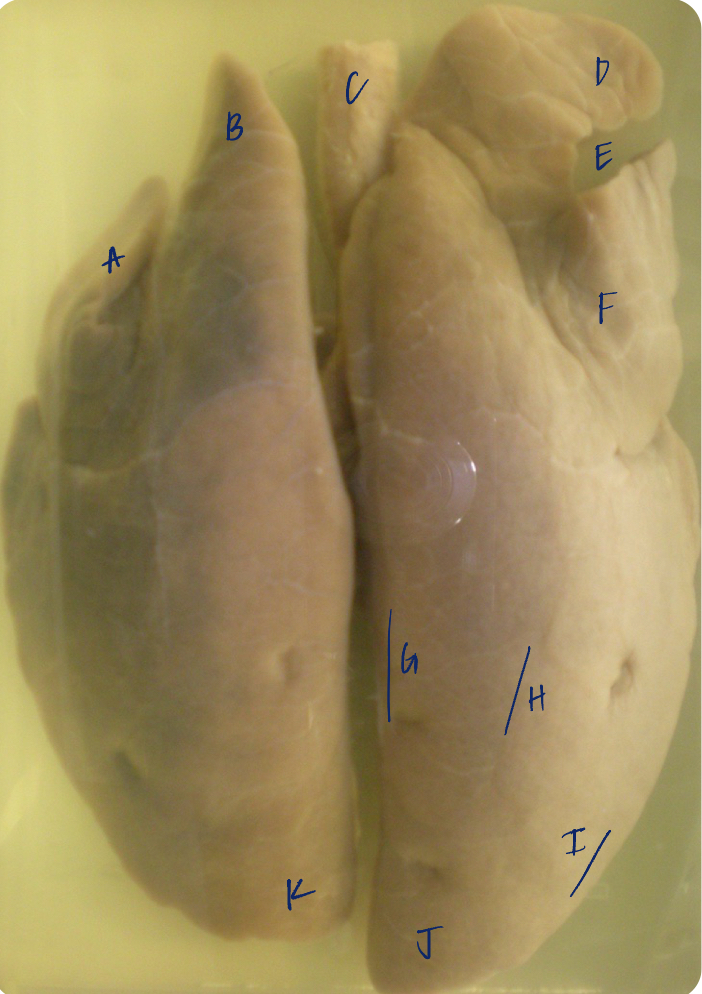

A

(cat larynx/trachea/lungs, dorsal)

epiglottis

B

(cat larynx/trachea/lungs, dorsal)

larynx

C

(cat larynx/trachea/lungs, dorsal)

trachea

D

(cat larynx/trachea/lungs, dorsal)

R cranial lobe

E

(cat larynx/trachea/lungs, dorsal)

middle lobe

F

(cat larynx/trachea/lungs, dorsal)

R caudal lobe

G

(cat larynx/trachea/lungs, dorsal)

primary bronchi

H

(cat larynx/trachea/lungs, dorsal)

L caudal lobe

I

(cat larynx/trachea/lungs, dorsal)

L cranial lobe

J

(cat larynx/trachea/lungs, dorsal)

cricoarytenoideus dorsalis m

K

(cat larynx/trachea/lungs, dorsal)

thyroid

A

(cat larynx/trachea/lungs, dorsal)

epiglottis

B

(cat larynx/trachea/lungs, dorsal)

larynx

C

(cat larynx/trachea/lungs, dorsal)

trachea

D

(cat larynx/trachea/lungs, dorsal)

R cranial lobe

E

(cat larynx/trachea/lungs, dorsal)

middle lobe

F

(cat larynx/trachea/lungs, dorsal)

R caudal lobe

G

(cat larynx/trachea/lungs, dorsal)

primary bronchi

H

(cat larynx/trachea/lungs, dorsal)

L caudal lobe

I

(cat larynx/trachea/lungs, dorsal)

L cranial lobe

J

(cat larynx/trachea/lungs, dorsal)

cricoarytenoideus dorsalis m

K

(cat larynx/trachea/lungs, dorsal)

thyroid